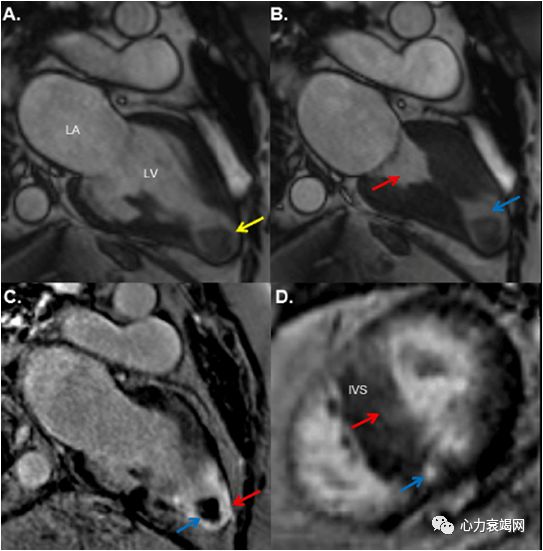

左室室间隔中远段及侧壁中段室壁增厚,致左室中部梗阻(最厚约19~20mm)

心尖部室壁变薄,可见矛盾运动

延迟增强后心尖部可见明显透壁样强化

印象:肥厚性心肌病,左室心尖部室壁瘤形成

左心室中部肥厚型梗阻性心肌病是HCM中的少见类型,发生率约占肥厚型心肌病的 l% ~10%

特征:左心室中部乳头肌与室间隔中部心肌异常肥厚,伴左心室心尖部与基底部心腔间存在压差

左心室中部收缩期梗阻或闭塞呈“沙漏形”或“哑铃形

易合并心尖室壁瘤、室性心动过速等心律失常,从而发生猝死,较普通肥厚梗阻心肌病预后更差